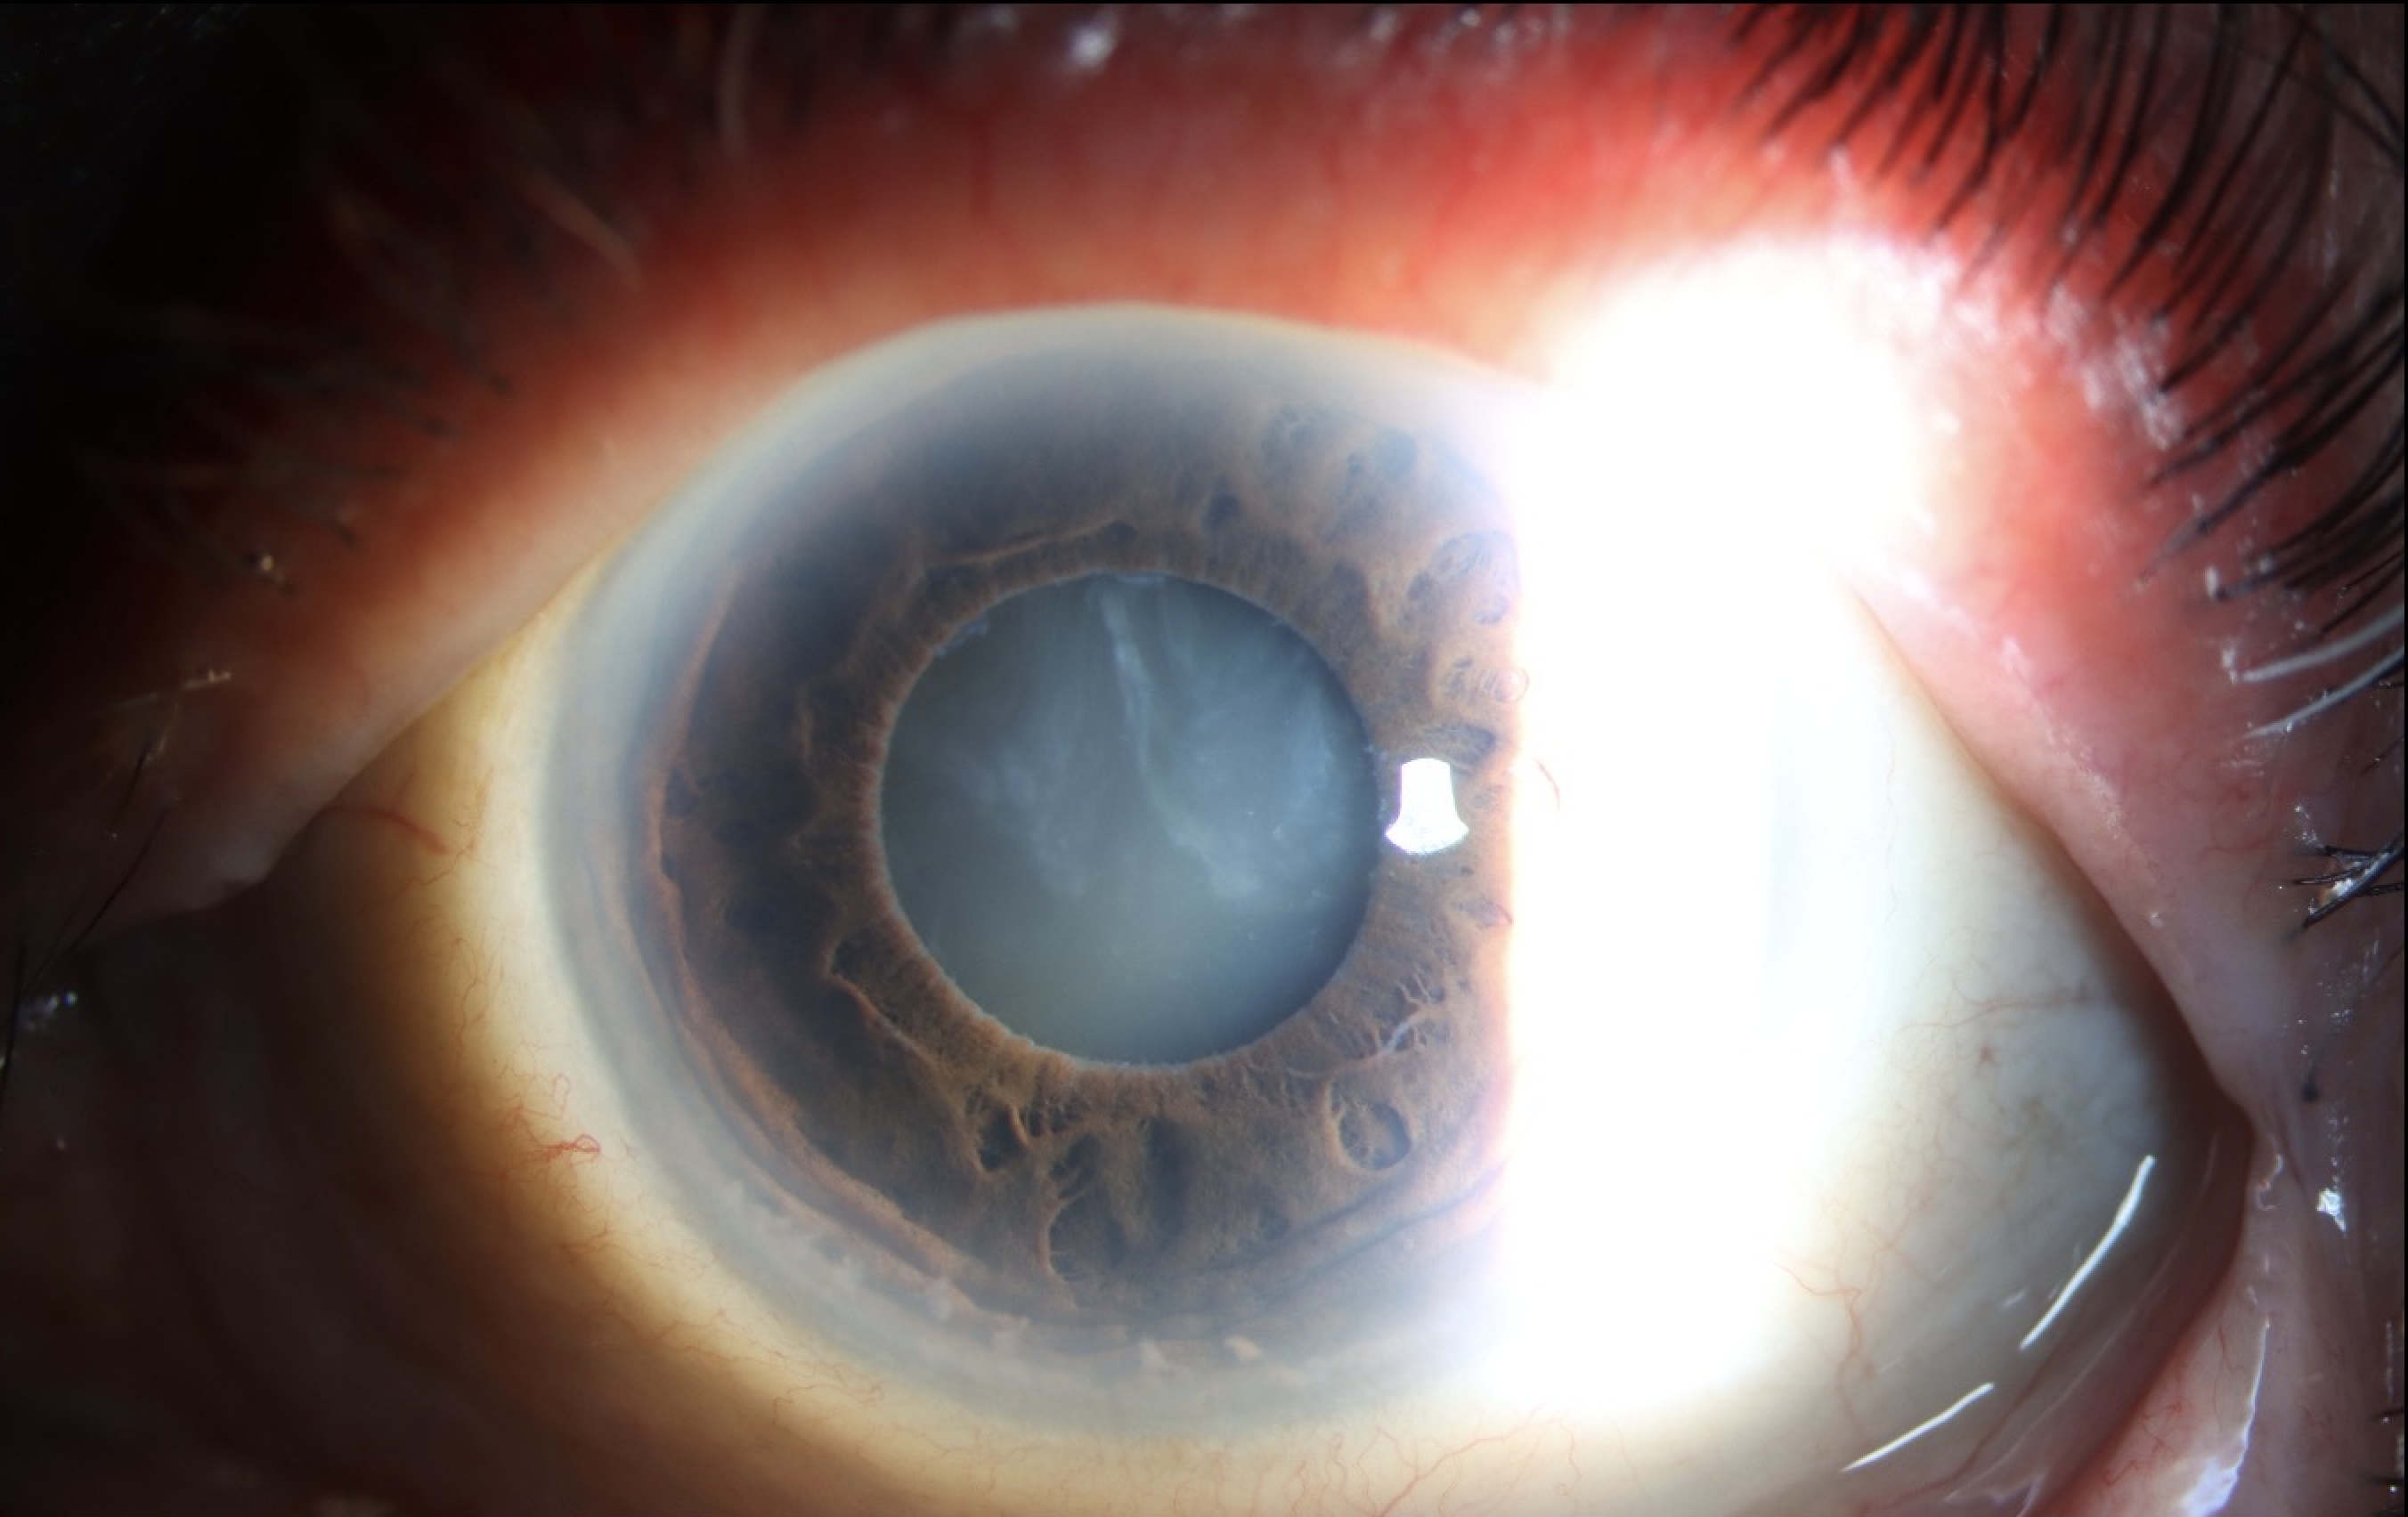

Morgagnian Cataract, Pseudoexfoliation Syndrome, Phacolytic Glaucoma

Specialty: Cataracts and Intraocular Lenses

Type: Ophthalmic Images

Include in Catalogue?: Yes

Original Contributor(s): Jesse D. Sengillo, MD; Jonathan D. Tijerina, MD, MA; Luiz E. Vazquez, MD, PhD

Presenter/Faculty: Sengillo, Tijerina, Vazquez

Slit lamp photos and UBM demonstrating a Morgagnian Cataract in a patient with Pseudoexfoliation Syndrome and Phacolytic Glaucoma.